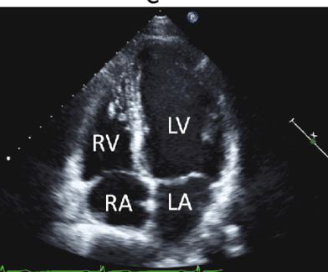

what view is this

apical 4 chamber

what can the a4c see and identify

pericardial effucion